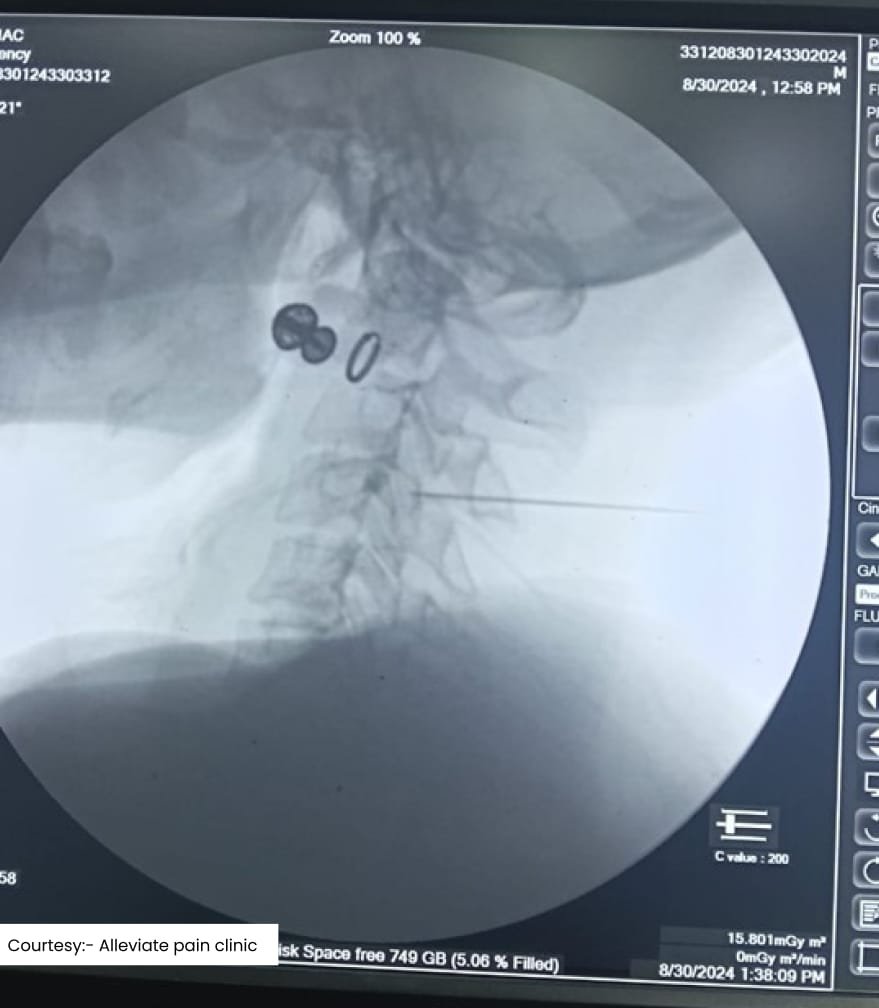

Scan2

Scan3

Fluoroscopic guided medial branch block for cervical facet joint syndrome sone at Alleviate Pain Clinic

Each of these procedures is performed using image guidance—such as fluoroscopy or ultrasound—to ensure precise needle placement and maximum effectiveness. This approach minimizes complications and maximizes pain relief.